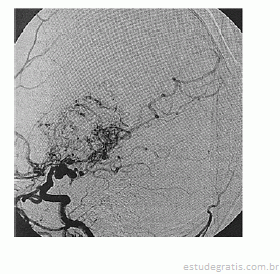

Paciente de 16 anos de idade, do sexo feminino, de asscendência japonesa, com deficits neurológicos progressivos iniciados ainda na infância, tem diagnóstico prévio de anemia falciforme. Realizou exame complementar de imagem do encéfalo, apresentado na reprodução acima. Há suspeita de doença de Moyamoya.

Em relação ao caso descrito, julgue os itens a seguir.

O envolvimento de ramos da artéria cerebral média e anterior com formação de vasos colaterais não é frequente.Comentários